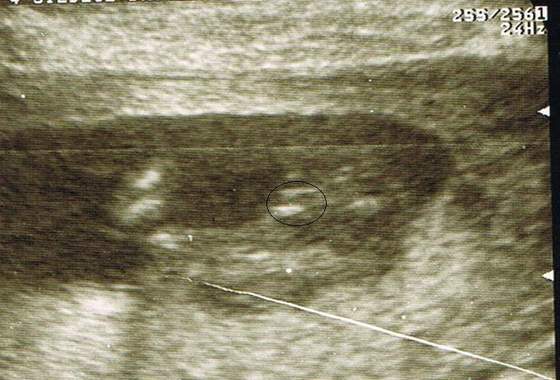

Tak więc od drugiego lekarza usłyszałam słowa: "optuję przy dziewczynce", dzidzia zdrowa, ruchliwa i mniejsza o tydz niż termin wg OM. Tak więc w tym momencie mam już 90% pewności a 10 % niepewności;-)( w końcu to już dwóch lekarzy).

Poprosiłam o zdjęcie i takie oto Pan doktor mi wręczył:

Chociaż szczerze to wczoraj USG było na dużo lepszym sprzęcie i kreseczki dużo lepiej było widać

Widzicie tu coś dziewczynki?